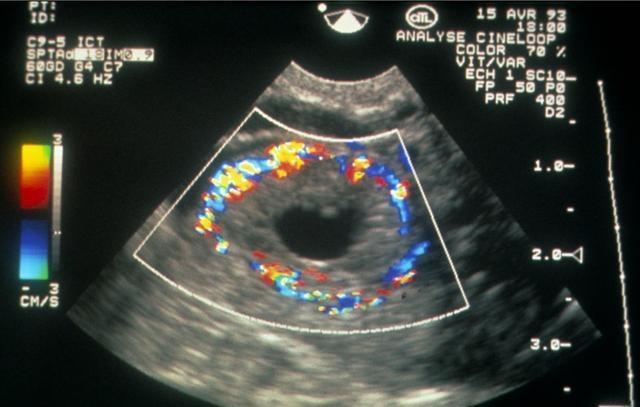

一、B超可以准确的确定准妈妈们是否怀孕:移植后第一次做B超主要是查看胚胎是否在子宫内,即判断是宫内孕还是宫外孕。其次通过查看孕囊大小、胚芽来判断胚胎发育状况。另外查看有几个孕囊,查看是单胎还是多胎。移植后14天左右做血检测hcg值判断是否怀孕是初诊,初诊确定怀孕后仍有生化妊娠的可能,移植后30天左右做B超检测是确诊。为物理妊娠。表示实际看到的怀孕。

如果试管婴儿移植成功怀孕,因为试管婴儿移植日相当于自然怀孕的15天左右,因此,检测试管婴儿是否怀孕通常在试管婴儿移植后14天做血检,然后试管婴儿移植后1个月左右做B超查看是否有孕囊,在试管婴儿移植后40-50天再次B超确定妊娠。

如果第二次B超检测到孕囊、胚芽、胎心正常,则说明试管婴儿成功。以后按照自然怀孕的孕期检查即可,可在当地进行检查。

4、移植后35天行阴道B超检查是否为宫内妊娠以及孕囊个数。出现孕囊、胎芽及原始心管搏动者为临床妊娠。宫外孕或多胎妊娠者应 及早处理。